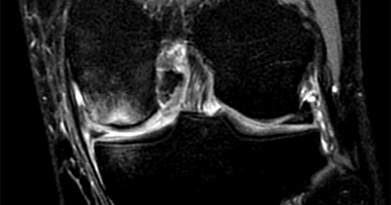

Arthroscopic surgery, is a surgical procedure to visualize, diagnose, and treat problems inside a joint using a specialized instrument known as an arthroscope. An arthroscope is a fiberoptic tube that contains a small lens or camera and a lighting system to magnify and illuminate structures inside a joint.